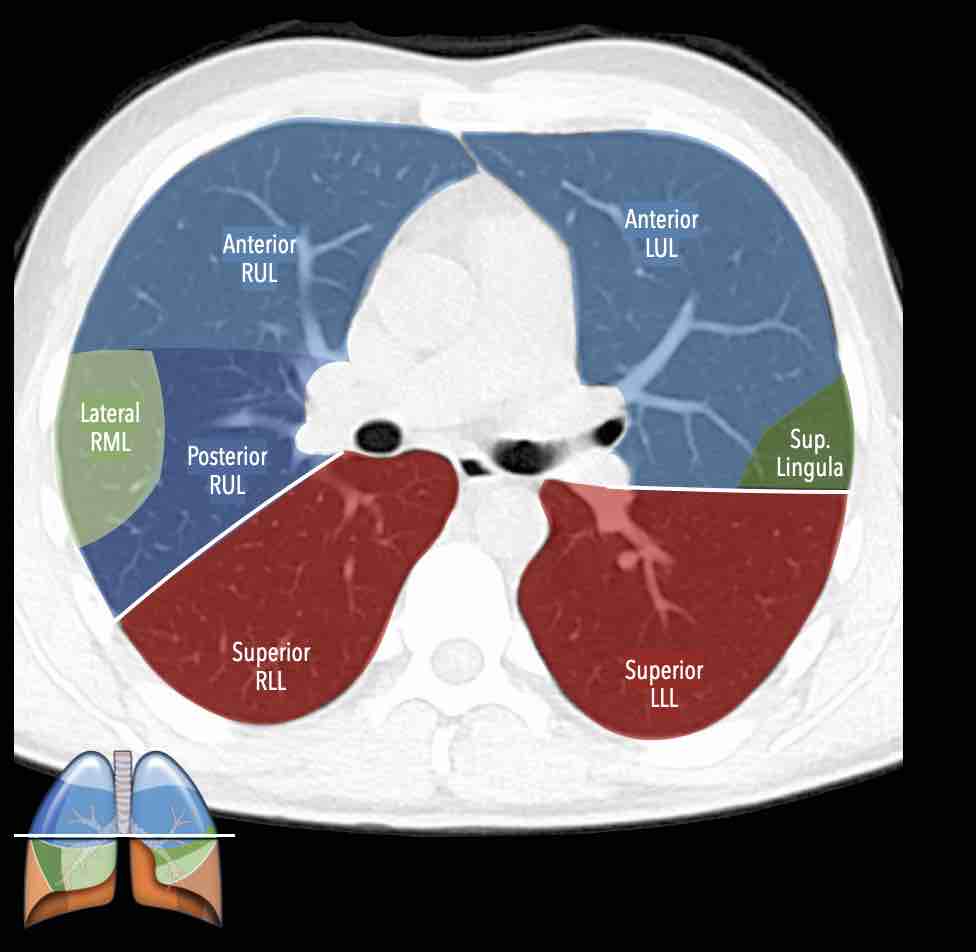

Các phân thùy phổi trên CT

Cuộn qua các hình ảnh để quan sát cách phổi được phân chia thành các phân thùy.